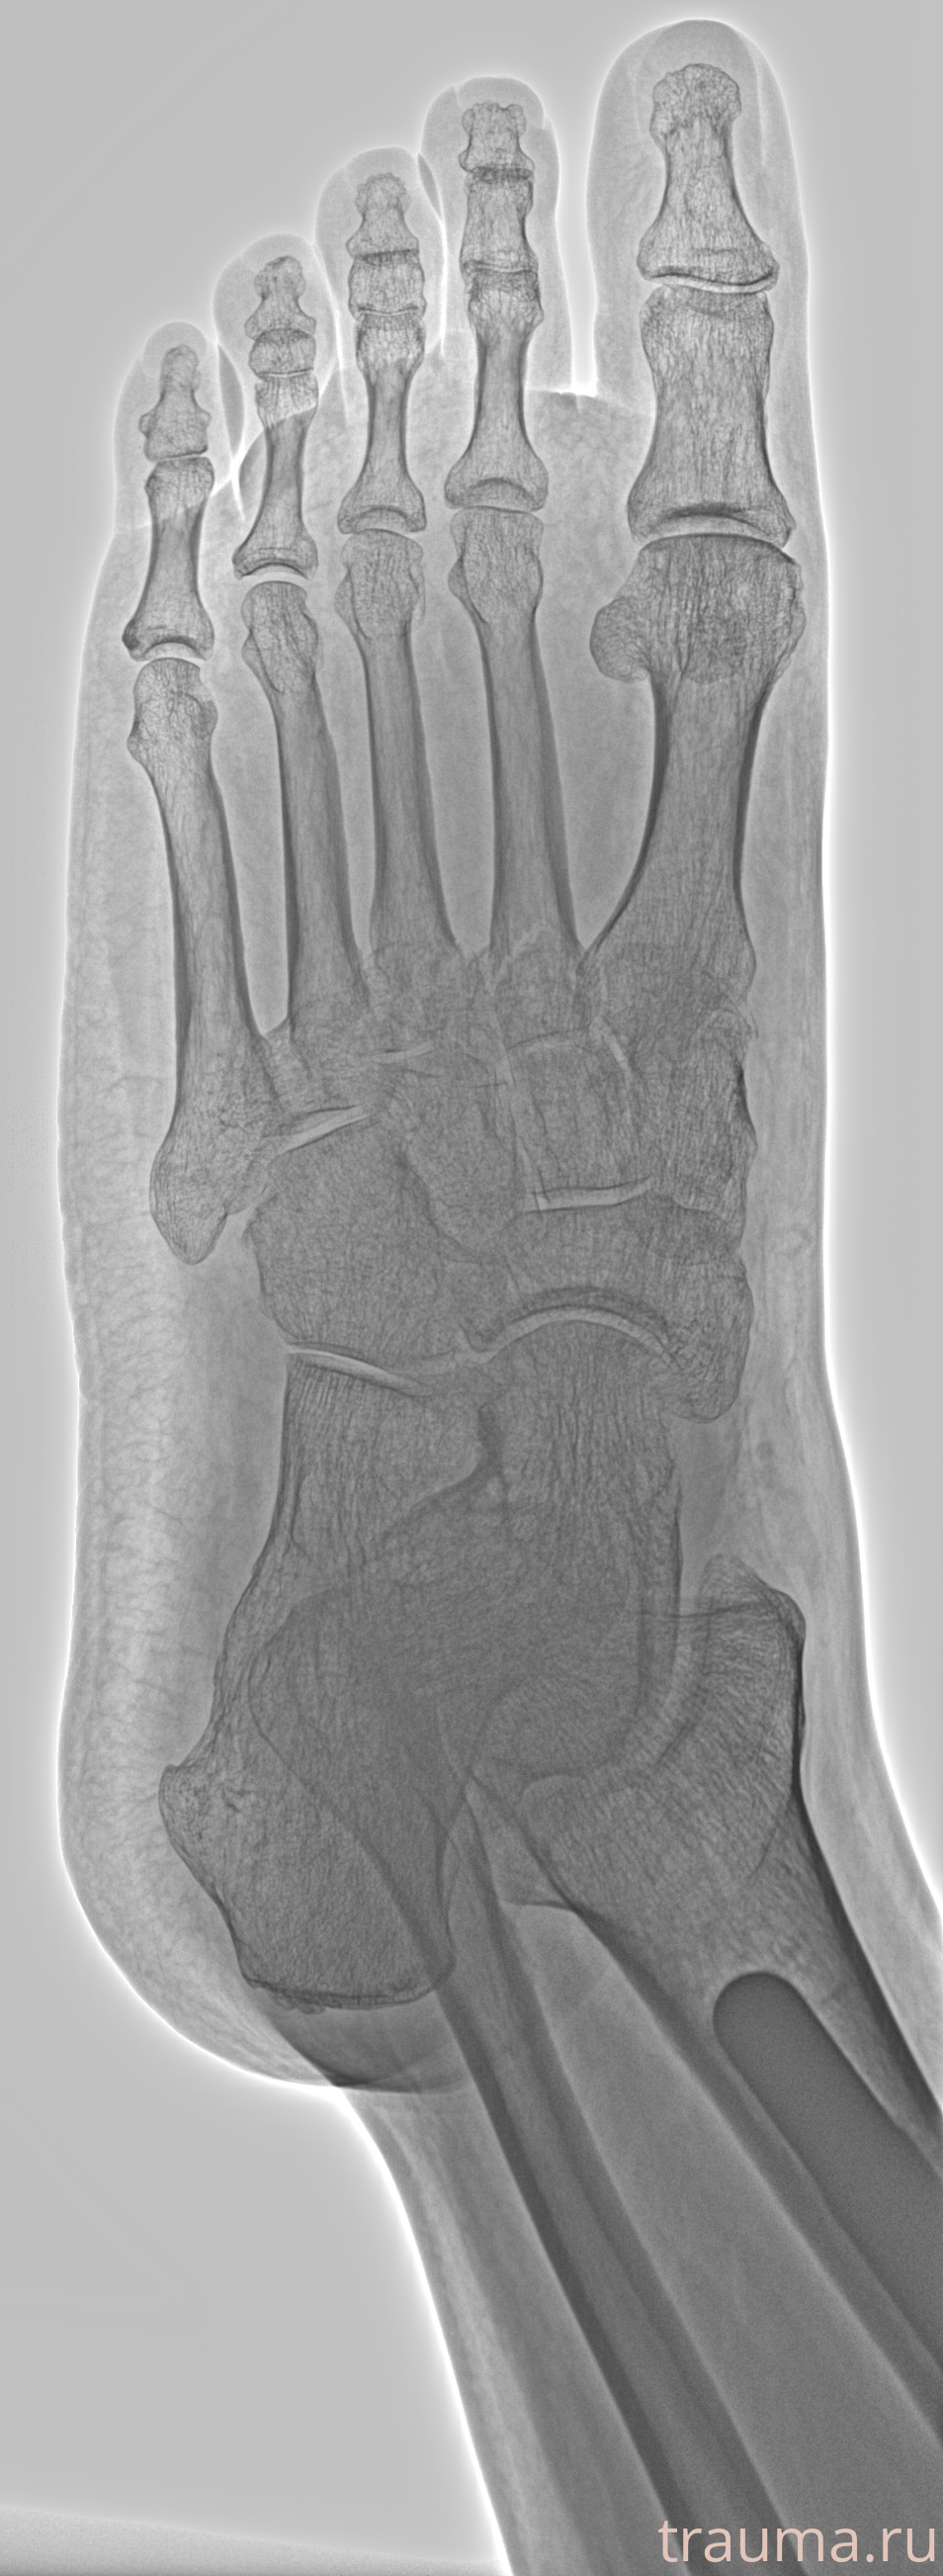

Рентгенограммы

Рентген на дому: по вашему адресу приезжает врач-рентгенолог, травматолог-ортопед с мобильным рентгеновским аппаратом, проводит диагностику травмы или заболевания, делает необходимые рентгенограммы, дает рекомендации по дальнейшему лечению. Получить качественные снимки в домашних условиях возможно благодаря уникальной методике, разработанной МосРентген Центром для института  Склифосовского